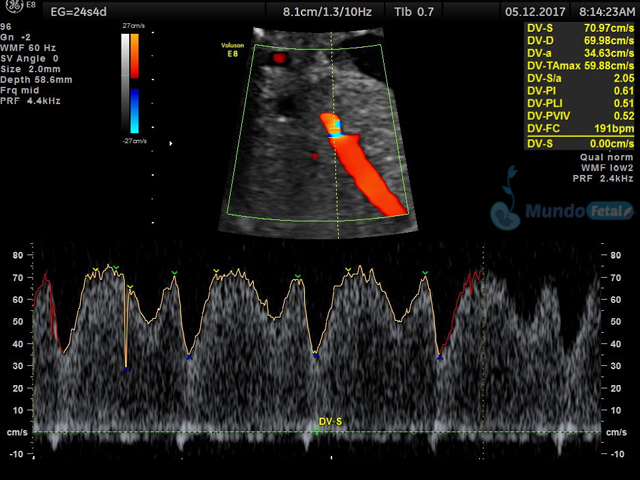

Se recomienda de 32-34 semanas, realizando valoración de crecimiento armónico (4 medidas específicas), valoración anatómica, líquido amniótico, flujos sanguíneos fetales y placentarios perfilando el bienestar fetal hacia el final de embarazo.